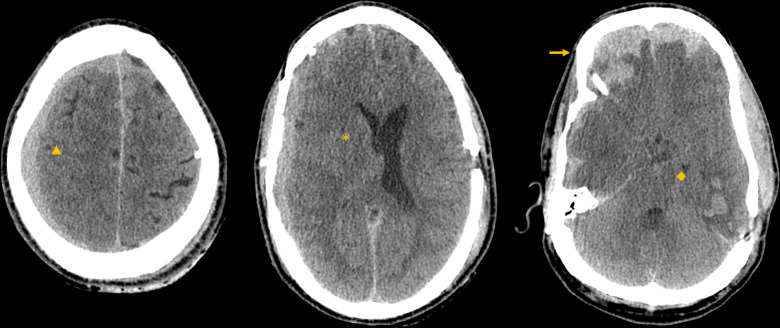

Fatal neurological deterioration after minor head trauma in a patient with prior neurosurgical intervention: a gap in the brain injury guidelines?

Abstract Image